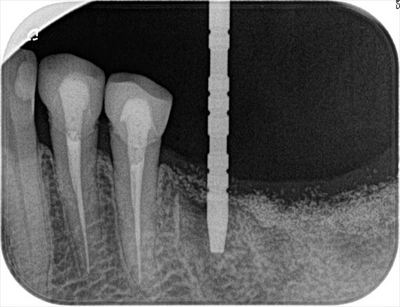

サージカルステントを用いてパイロットドリルでドリリングし深度ゲージを挿入して

レントゲンを撮影します。

![]()

デンタルX線写真です。

予定通りの位置・角度にドリリングできていますのでドリルステップを進めます。